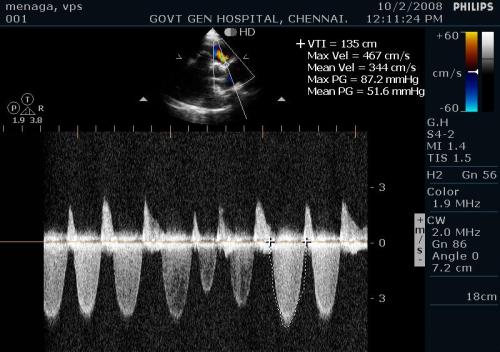

Estimating Pulmonary artery pressure

PA systolic pressure : TR jet + 10 mmhg

Note the peak TR jet is around 50mmhg and predicted RVSP would be 60mmhg.One would have expected still higher RV pressure but since the RV is dysfunctional the true PAP may be underestimated.